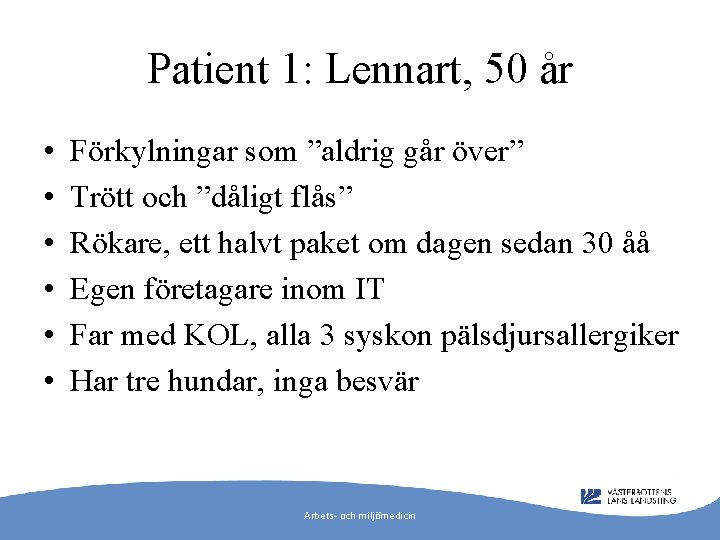

Patient 1: Lennart, 50 år • • • Förkylningar som ”aldrig går över” Trött och ”dåligt flås” Rökare, ett halvt paket om dagen sedan 30 åå Egen företagare inom IT Far med KOL, alla 3 syskon pälsdjursallergiker Har tre hundar, inga besvär Arbets- och miljömedicin

Patient 1: Lennart 50 år • • FEV 1 VC FEV% 3, 15 L (81%) 5, 0 L (105%) 5, 2 L (109%) 0, 61 (61%) • Efter reversibilitetstest: FEV 1 3, 6 L (92%) och FEV% 69%. VC och FVC oförändrade. • 14% förbättring, 450 ml Arbets- och miljömedicin

Diagnos? • Astma, men kvarstående obstruktivitet efter rev -test • Gått obehandlad länge? • Astma med KOL (pga rökning eller obehandlad astma? ) • Rökstopp, läkarbedömning Arbets- och miljömedicin